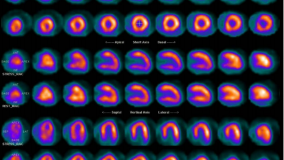

SPECT/CT Atlas of Quality Control and Image Artefacts

2019